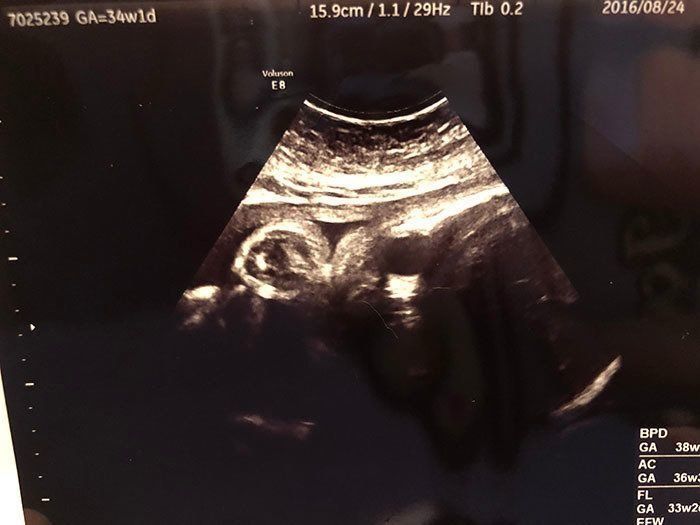

妊娠34週目 予定日が近づき、気持ちが落ち着かない日々

妊娠34週目の健診日。仕事を辞めたせいか、幸いにも血圧は平常値に。安静を心がけ外出は控えましたが、運動不足の解消を兼ねて、ベビーベッドの組み立てやベビーアイテムの収納作りをして過ごしていました。